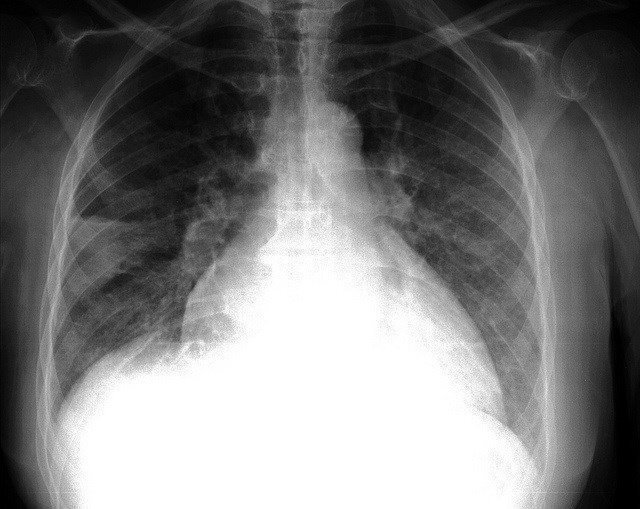

Valdecilla desarrolla un estudio nacional para detectar infecciones en pacientes trasplantados de pulmón

El Servicio de Medicina Intensiva del Hospital Universitario Marqués de Valdecilla ha desarrollado un estudio nacional para detectar precozmente las infecciones en pacientes trasplantados de pulmón mediante nuevos marcadores sanguíneos.

Los resultados de este trabajo, publicados en la prestigiosa revista 'PlosOne', han puesto de manifiesto la utilidad de la procalcitonina (una proteína presente en la sangre) como método para diagnosticar la existencia de un proceso infeccioso en el postoperatorio inmediato del trasplante pulmonar, ha informado el Gobierno de Cantabria en nota de prensa.

Bajo la dirección del doctor Borja Suberviola, médico del Servicio de Medicina Intensiva de Valdecilla, y en colaboración con los centros hospitalarios de España que realizan trasplante pulmonar, este estudio ha revelado que la cuantificación de esta proteína podría ayudar a seleccionar a aquellos pacientes que están desarrollando una infección, optimizando su tratamiento y controlando el proceso infeccioso en fases muy iniciales y antes de que repercuta en el pronóstico del paciente.

Según los expertos, el trasplante pulmonar es la intervención de órgano sólido que cuenta con la esperanza de vida más reducida, debido en parte a las complicaciones que se presentan en los primeros días de postoperatorio del trasplante.

Entre ellas, las más importante son la infección y la disfunción primaria del injerto; dos entidades con formas de presentación muy similares y en ocasiones de difícil diferenciación, pero que cuentan con formas tratamientos diferentes. En el caso de las infecciones, un diagnóstico y tratamiento precoces son fundamentales para lograr una evolución satisfactoria y la resolución del cuadro.